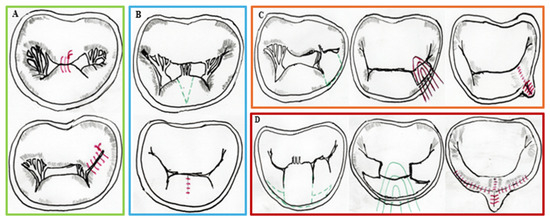

The treatment of mitral valve disease remains dynamic. The literature has previously shown the great advantage of mitral valve repair over replacement, especially in degenerative mitral valve disease. Since the introduction of the “French Correction” by Carpentier, which remarks the importance of leaflets’ resection, new concepts in leaflet repair techniques have emerged; these modifications have the final goal of the minimization of leaflet resection, focusing on techniques for leaflet remodeling and neochordae implantation.

In this scenario, recently, there has been a rapid adoption and implementation of transcatheter alternatives for mitral valve disease, including transcatheter edge-to-edge repair, transapical neochordal implantation and percutaneous annuloplasty (directly, or indirectly through coronary sinus remodeling). Finally, transcatheter alternatives for mitral valve replacement are emerging.